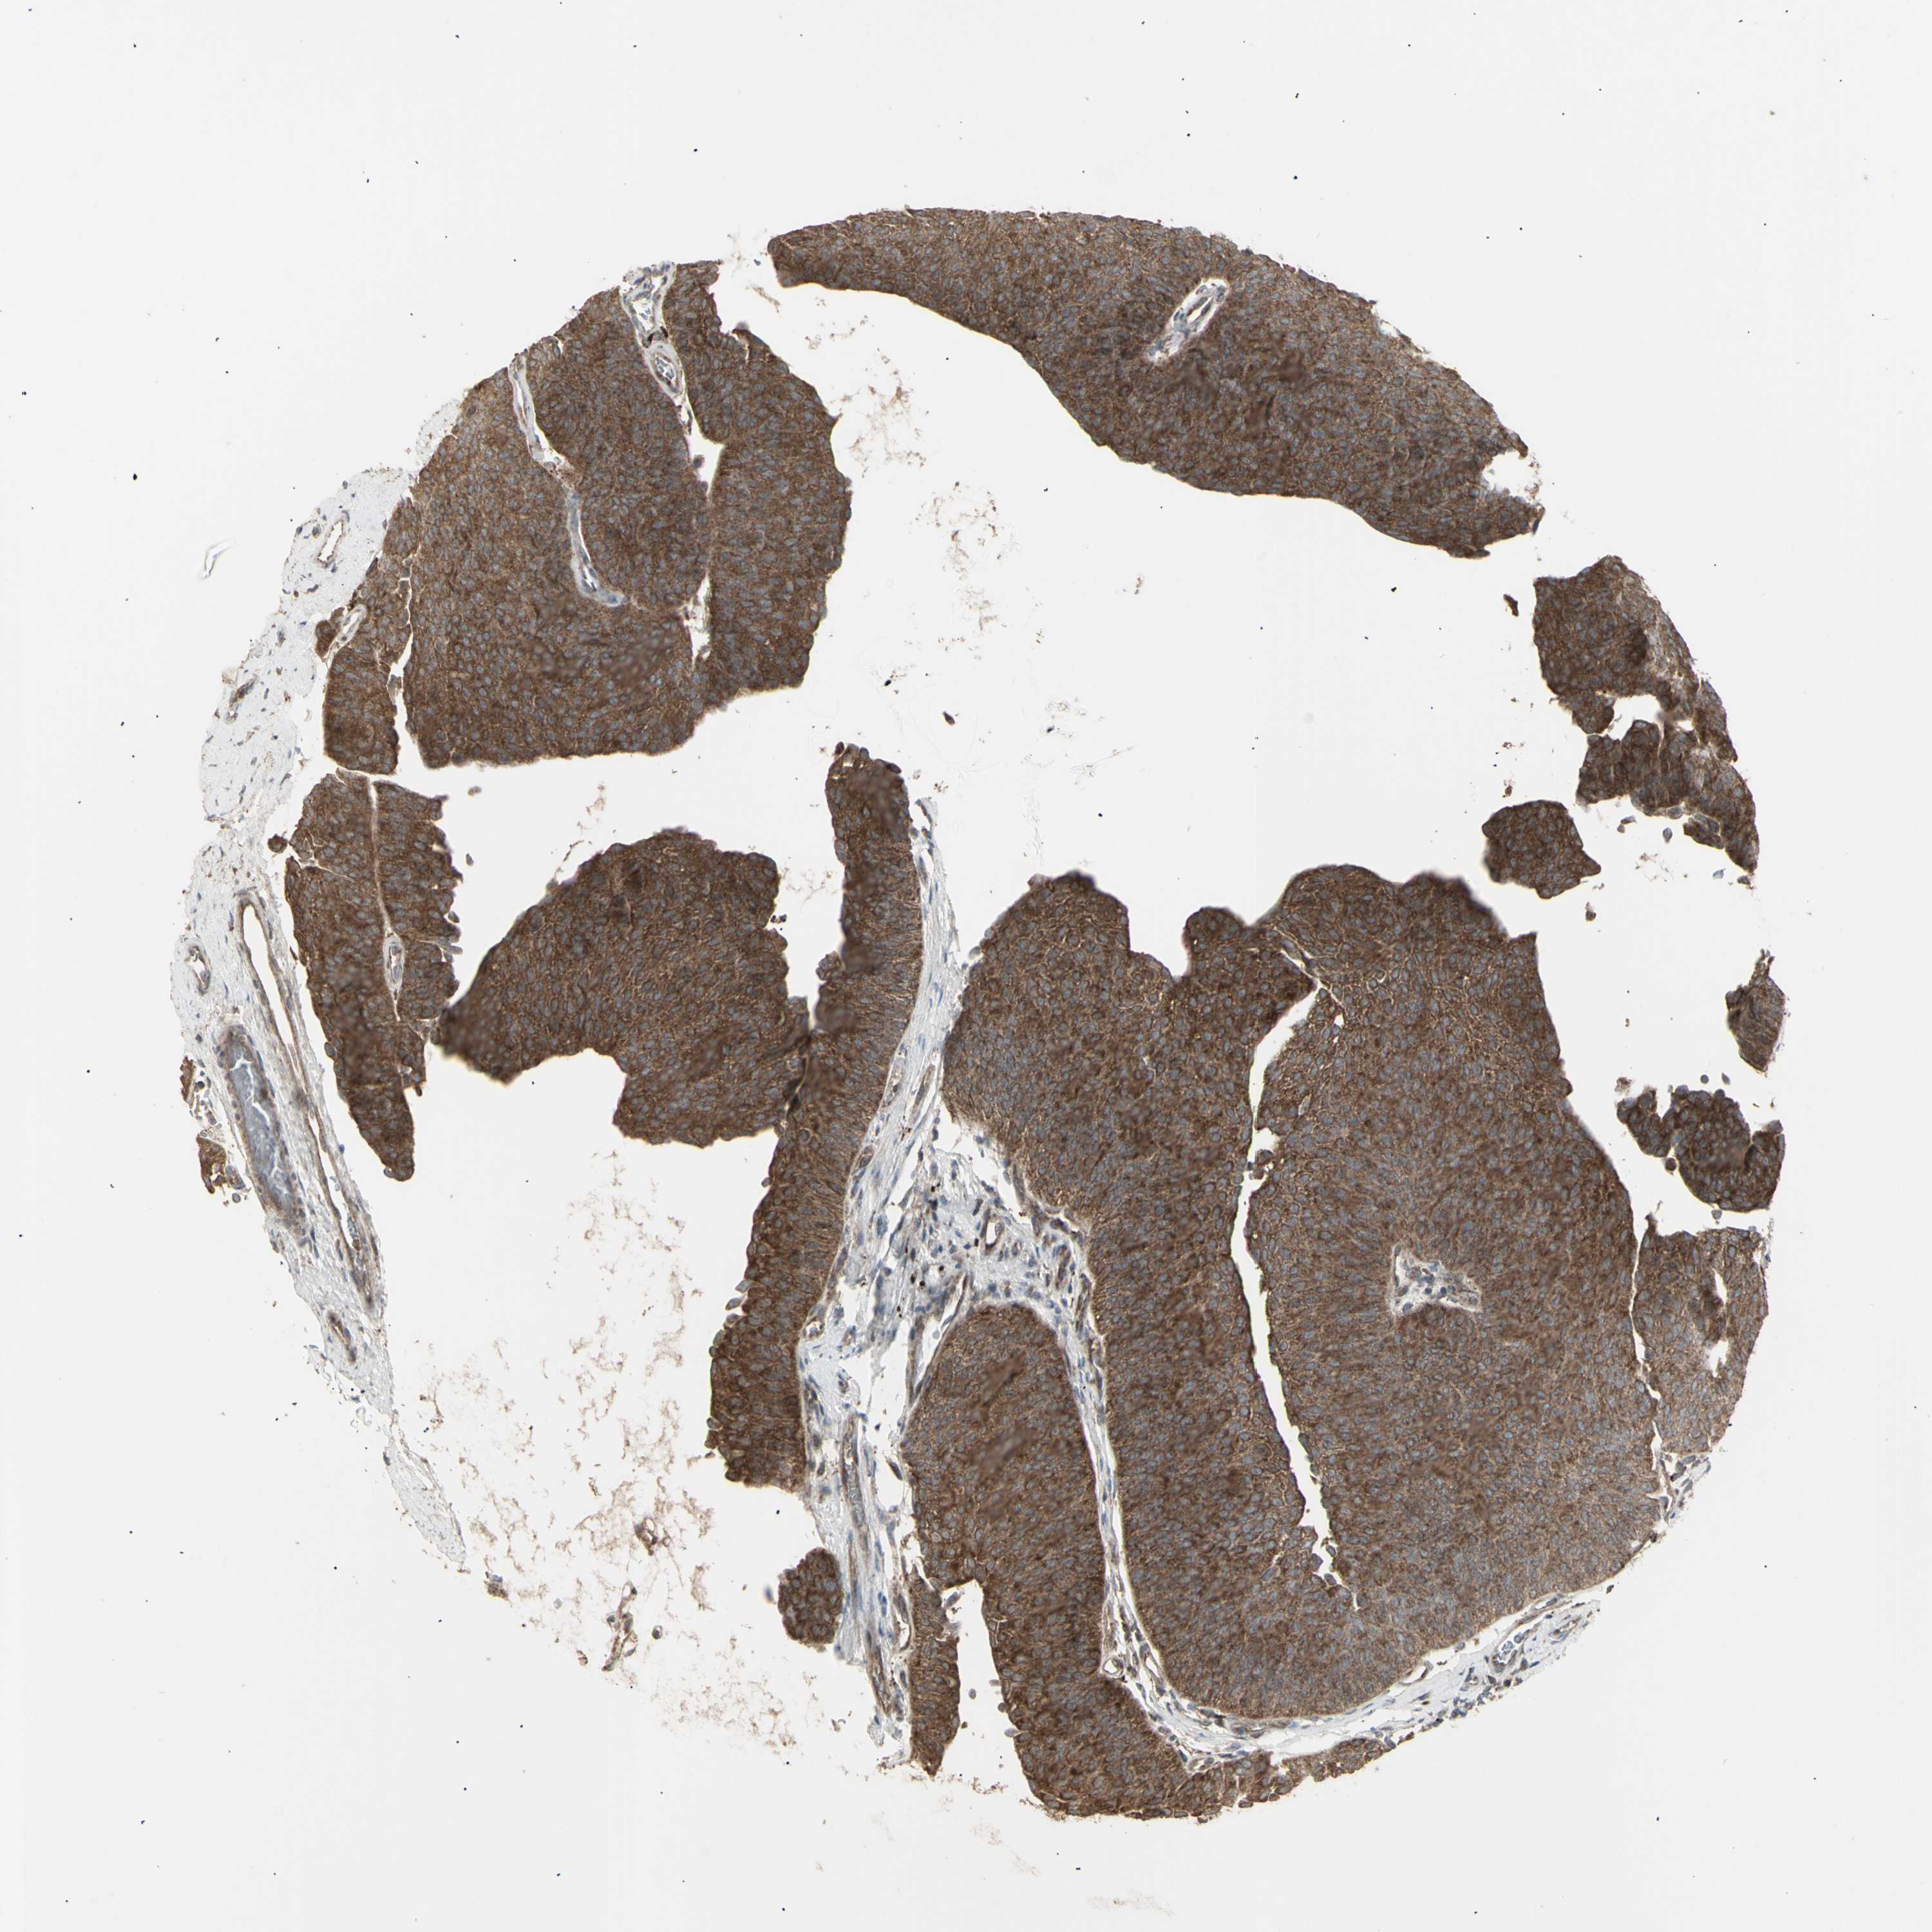

UROTHELIAL CANCER - Protein expressioni

A mouse-over function shows sample information and annotation data. Click on an image to view it in a full screen mode. Samples can be filtered based on level of antibody staining by selecting one or several of the following categories: high, medium, low and not detected. The assay and annotation is described here.

Note that samples used for immunohistochemistry by the Human Protein Atlas do not correspond to samples in the TCGA dataset.

Antibody stainingi

Antibody staining in the annotated cell types in the current human tissue is reported as not detected, low, medium, or high, based on conventional immunohistochemistry profiling in selected tissues. This score is based on the combination of the staining intensity and fraction of stained cells.

Each image is clickable and will lead to virtual microscopy that enables deeper exploration of all samples and also displays staining intensity scores, fraction scores and subcellular localization as well as patient and tissue information for each sample.

Antibody HPA002633

Antibody HPA046758

Antibody CAB010906

Staining

High

Medium

Low

Not detected

Intensity

Strong

Moderate

Weak

Negative

Quantity

>75%

75%-25%

<25%

None

Location

Nuclear

Cytoplasmic/membranous

Cytoplasmic/membranous,nuclear

Urothelial carcinoma, High grade

Urothelial carcinoma, Low grade